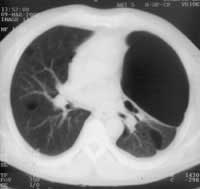

Рентгенография буллезной болезни легких не позволяет получить анатомическую и функциональную характеристику легкого, необходимую для успешного хирургического лечения заболевания. Буллезное перерождение легких выявляется на рентгенограммах в виде бессосудистых участков повышенной прозрачности, окруженных дугообразными тонкими тенями (Рис. 1а). Некоторую информацию функционального характера можно получить путем сравнения рентгенограмм на вдохе и выдохе. При наличии множества булл, крайне трудно разобраться в сети переплетающихся теней.

Рис. 1. (а) Левое легкое поджато гигантской буллой, симулирующей спонтанный пневмоторакс. Отмечается смещение средостения вправо.